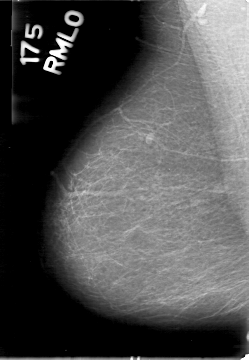

D_4028_1.RIGHT_MLO

RIGHT_MLO LINES 5386 PIXELS_PER_LINE 3721 BITS_PER_PIXEL 12 RESOLUTION 43.5 NON_OVERLAY